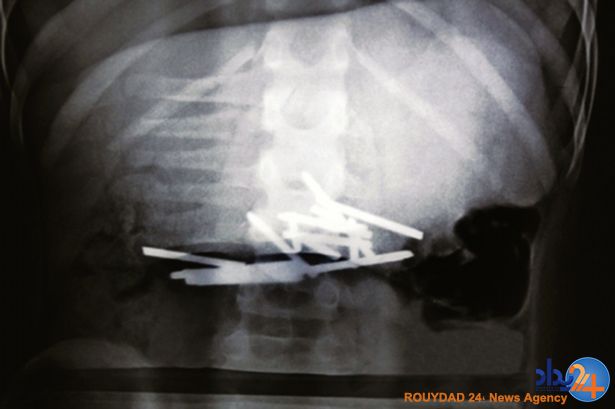

12 میخ در شکم پسربچه 10 ساله چینی (تصاویر)

پسربچه 10 سالهای که 12 میخ فولادی را بلعیده بود، باعجله به بیمارستان رسانده شد.

به گزارش رویداد۲۴ به نقل از دیلی میرور، پزشکان پسازآنکه دریافتند این پسر 10 ساله در مقابل چشمان همکلاسیهایش میخهایی با قطر 3.5 سانتیمتر را بلعیده، بسیار متعجب شدند.

این پسر به نام ژیائو ون که در استان هونان چین زندگی میکند، برای عکسبرداری از شکمش به بیمارستان منتقل شد.

پزشک معالج او گفت که سیتی اسکن از وجود 12 میخ در شکم ون خبر میدهد و ممکن بود این میخها آسیب جدی به اعضای داخلی بدن او بزند.